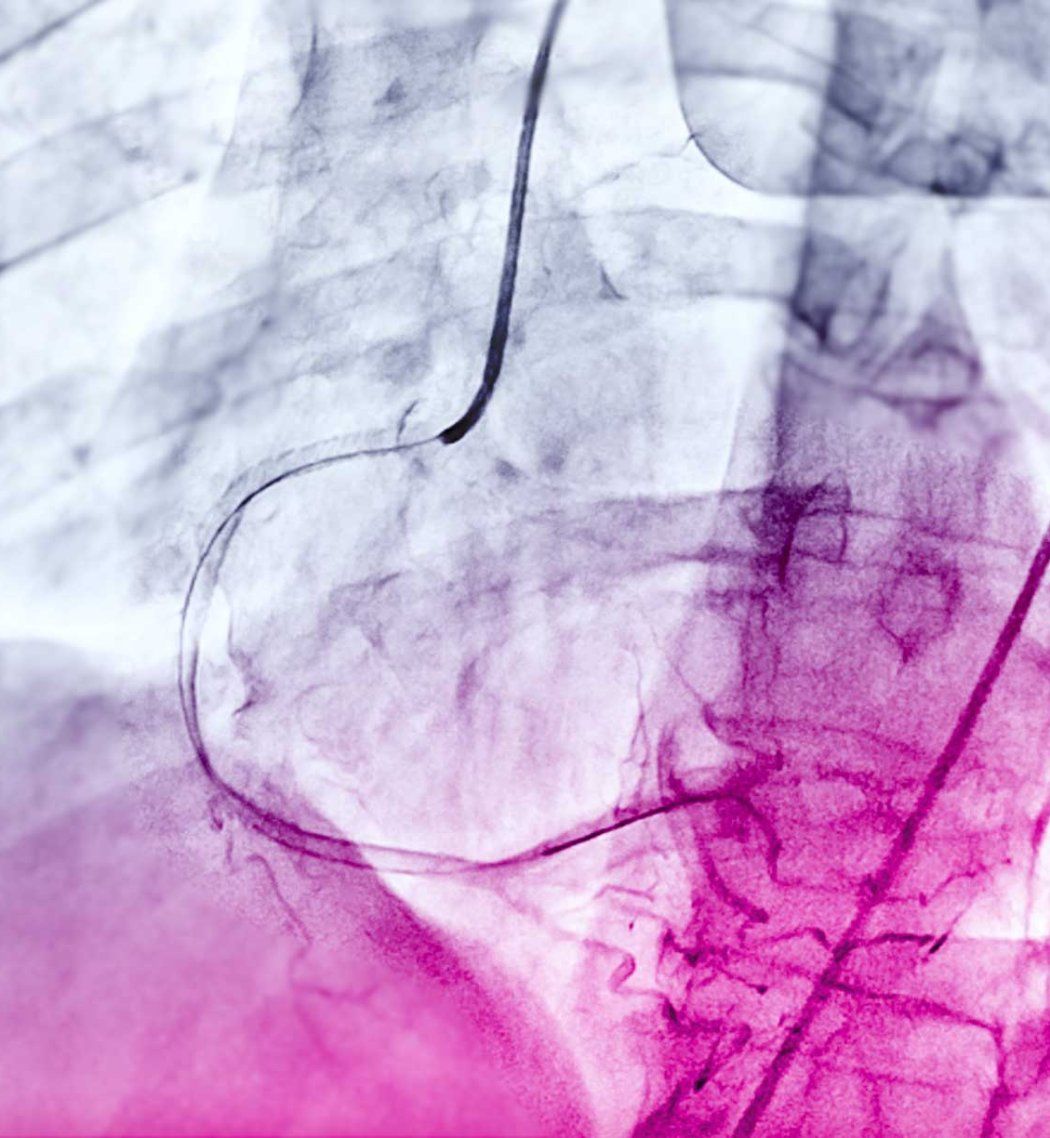

Angiograms much like this could one day be used to diagnose more serious cardiac issues without further risky testing.

Physicians commonly use a test called a coronary angiogram to diagnose the condition. As part of angiograms, physicians inject a special dye into the main vessels that feed the heart to see how blood flows using x-rays.